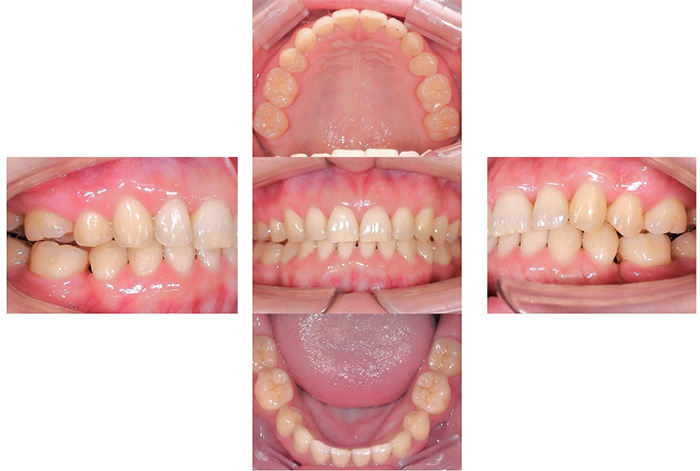

前歯の見た目と噛み合わせのバランスを整えたケース

今回の患者様は、ディープバイト(過蓋咬合)による前歯の見た目と噛み合わせを気にされて来院されました。ディープバイトとは、上の前歯が下の前歯に深く重なっている噛み合わせのことで、見た目の問題だけでなく、前歯や顎への負担につながることがあります。

本症例では、マウスピース型矯正装置(インビザライン)を用いて治療を行いました。合計84枚のアライナーを使用し、歯並びだけでなく咬合の深さにも配慮しながら治療を進めました。

治療後は、前歯の見た目のバランスが整い、噛み合わせも改善しました。

インビザラインによる全体矯正後に補綴治療を行い、咬合と審美性を総合的に改善した症例です。

まずマウスピース型矯正装置(インビザライン)により歯列および咬合関係を整え、その後、必要部位にジルコニア補綴を行いました。

矯正のみ・補綴のみではなく、両治療を組み合わせることで機能性と審美性の両立を目指した包括的治療です。

奥歯の噛み合わせと前歯の歯並びを同時に改善した症例(インビザライン+ジルコニア)

患者様は、奥歯でしっかり噛めないことと、前歯の歯並びの乱れを気にされ来院されました。診査の結果、前歯部の叢生(歯並びの乱れ)と、臼歯部の離開咬合(奥歯がしっかり噛み合っていない状態)が認められました。また、臼歯部には古い金属修復物が装着されており、機能面だけでなく審美面においても改善が必要な状態でした。

【治療後】

前歯の歯並びが整い、見た目の改善が認められました。また、奥歯でしっかり噛める状態となり、咬合機能の回復が得られています。

本症例では、歯並びの改善だけでなく、噛み合わせの回復と審美性の向上を同時に行っています。当院は一般歯科と矯正治療の両方に対応しているため、矯正治療後に別の医療機関で補綴治療を行う必要がなく、一貫した治療計画のもとで治療を完結することが可能です。また、奥歯の噛み合わせを矯正治療のみで改善する場合、治療期間が長くなることがありますが、本症例では補綴治療(アンレー)を併用することで、比較的短期間で咬合の改善を行いました。さらに、古い金属修復物をジルコニアに置き換えることで、見た目の改善と機能性の両立を図っています。